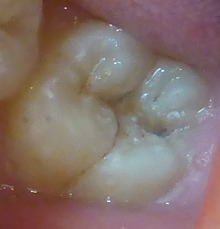

下の写真は12歳の男の子です。

通常は 麻酔をして タービンと呼ばれる

ドリルで、黒い部分を削り取ります。